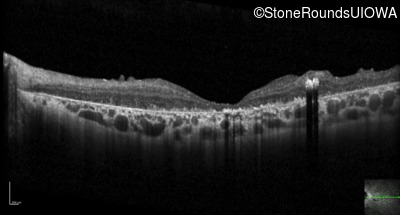

Optical Coherence Tomography - Right - 10/700 sc

Exemplar / OCT Stack